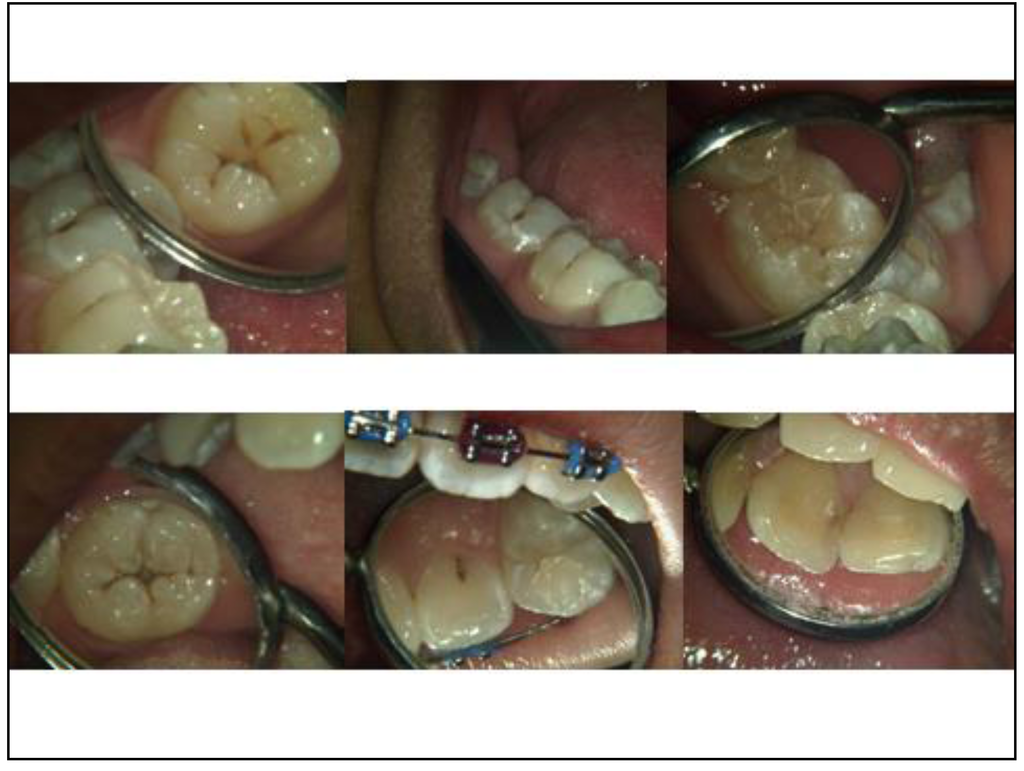

The next step was to start selecting and collecting appropriate extracted teeth with various stages of caries lesions. They were cleaned and their digital images taken with the Camsight digital surgical scope camera (Figure 2). Photographs were also taken of carious teeth seen clinically in patients’ mouths (Figure 3). That began the creation of a collection of training resources and tools at IMU.

Figure 3. Camsight digital images of patients’ teeth depicting different ICDAS codes.